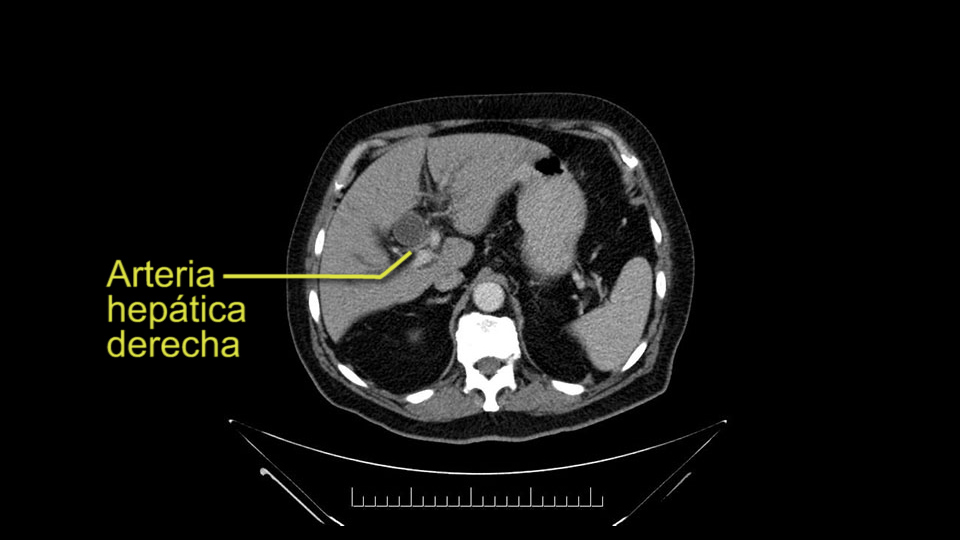

He has normal arterial anatomy: no accessory or replaced right hepatic artery, which is important because sometimes the right hepatic artery can come behind the neck of the pancreas and you have to be careful of that in a Whipple dissection.

Then you look for anomalies. The one you worry about the most doing a Whipple is a replaced or aberrant right hepatic artery coming off the SMA at its origin. So again, find the SMA. You can find it because the renal vein goes through it. Follow it up, up-up-up. Nothing coming off of there that I can see here. Nothing coming off of it, nothing coming off of it and just to confirm it, look at the celiac trfurcation. There’s the celiac, there’s the bifurcation, there's the splenic artery, hepatic artery. Make sure there’s a right, which there is here. The right usually goes under the bile duct: important when you’re going around the bile duct to do a Whipple. A replaced right goes under the portal vein and the bile duct way over here on the right. That’s about it.

To plan a pancreatoduodenectomy, we start by reviewing the vascular anatomy, especially the origin of the celiac trunk, here, in front of the aorta, looking for any evidence of stenosis. In addition, we look at the origin of the superior mesenteric artery, to look for any branches, and any replaced right hepatic arteries coming from the superior mesenteric artery; which does occur in about 12% of the population.

The second point about the vascular anatomy-, is to again look for right hepatic arteries in the hilum, coming from the superior mesenteric artery by palpating-through the Winslow Hiatus. Usually we will check for a pulse in the posterior aspect of the hepatic hilum, where a right hepatic artery should not usually be found. In this case, the precaution is to avoid an accidental ligation of the right hepatic artery that might jeopardize perfusion of the right lobe, or if there is a completely replaced hepatic artery that can put the liver circulation at risk.

Para planear una pancreatoduodenectomía, se debe revisar la anatomía vascular, especialmente el origen del tronco celíaco, aquí, por delante de la aorta, buscando areas de estenosis y por otro lado, el origen de la arteria mesentérica superior, para evaluar -sobre todo- si hay ramas, arterias hepáticas derechas provenientes de la mesentérica superior; lo cual ocurre en alrededor del 12% de la población.

E l segundo punto de la anatomía vascular, es nuevamente buscar arterias hepáticas derechas, en el hilio, provenientes de la mesentérica superior y eso lo hacemos palpando -a través del Hiato de Winslow- el hilio hepático y usualmente sentiremos un pulso en el aspecto posterior del hilio hepático, donde no debe ir el recorrido usual de la rama derecha de la arteria hepática. En este caso, la precaución es no realizar una ligadura accidental de la arteria hepática derecha y poner en riesgo -posiblemente- la perfusión del lóbulo derecho, o aún esta arteria puede reemplazar completamente la arteria hepática y poner en riesgo la circulación del hígado.

I am a believer in pylorus preservation. And in this case I see no reason why that wouldn't be possible. Mobilize the duodenum, divide the gastroepiploic vessels and divide the duodenum. I try to divide it with a linear stapler about four centimeters from the pylorus to have adequate length for my GI anastomosis. This facilitates exposure of the head neck of the pancreas. I find the gastroduodenal artery. This patient has normal arterial anatomy. Always on every preoperative CT scan I look to see if there is a replaced right hepatic. In this case I did not see one. Regardless of how confident I am I always look carefully for variant anatomy. I always do a clamp test on the GDA before ligation. I doubly ligate the GDA with not just a tie but a suture ligature because of the risk of GDA blowout in patients with a leak.